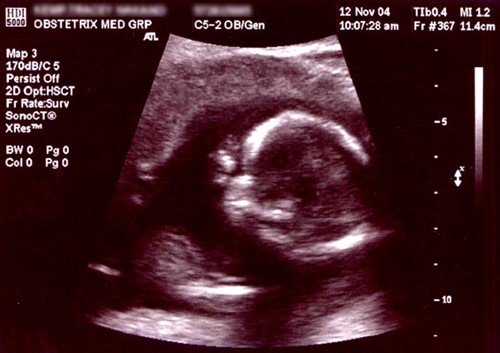

NIPS is a type of prenatal screening test that uses a simple blood test to check for any genetic abnormalities in a developing foetus. This test is considered non-invasive as it does not pose any threat or risk to the mother or her unborn baby. This test is performed in early pregnancy (around week 10) to determine the baby's risk of having chromosomal disorders or abnormalities.

NIPS is a safe and reliable prenatal screening method for most expectant mothers. It works by analysing foetal DNA in the mother's blood, collected at 10-13 weeks of pregnancy. This test helps parents make informed decisions about their pregnancy and the health of their developing baby.